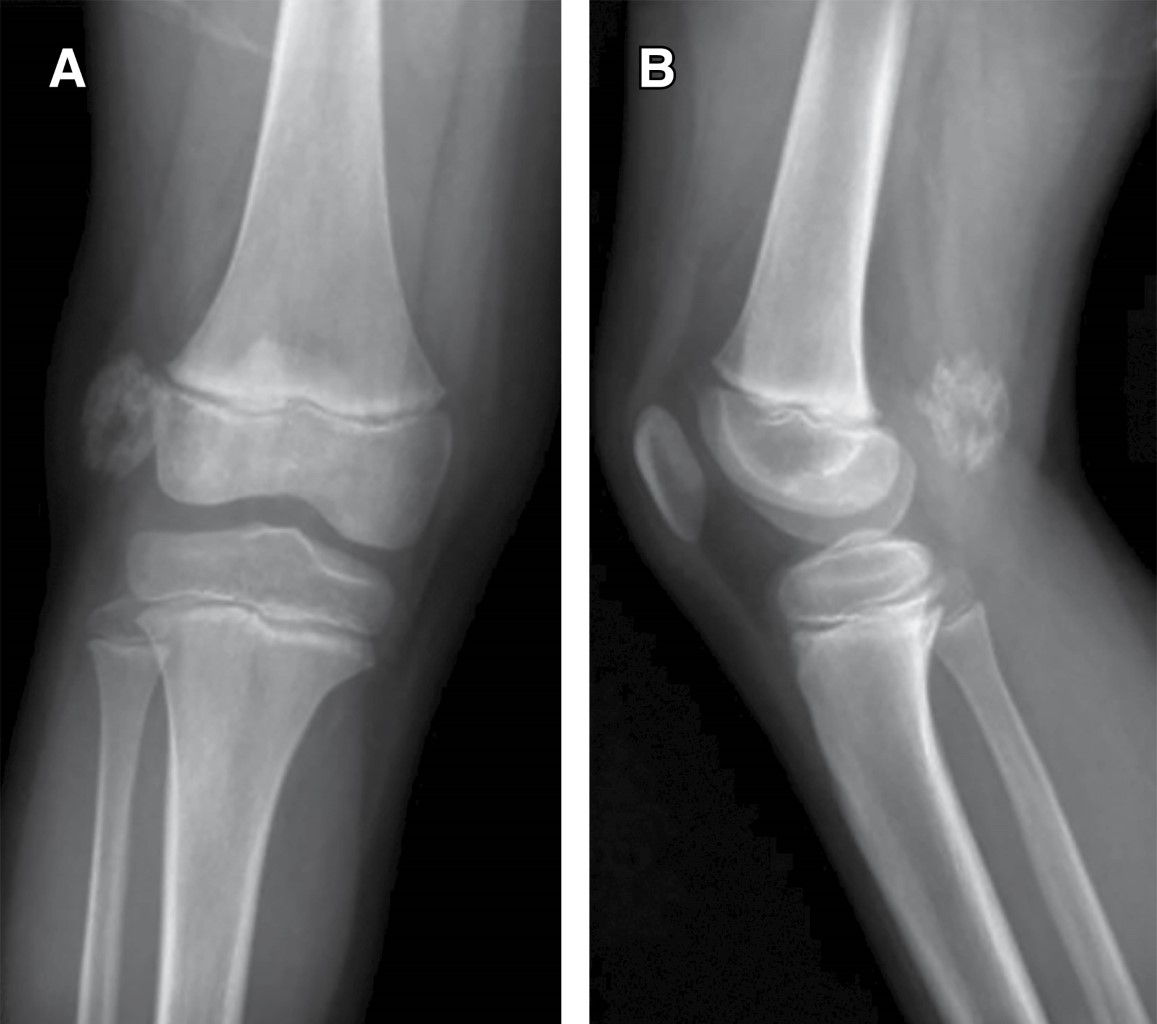

Introduction: myositis ossificans (MO) is described as a non-neoplasic heterotopic bone formation at soft tissues and muscle. It is a rare entity in children, but it must be included within the differential diagnosis of a malignant tumor or an infection. Material and methods: the objective of this retrospective study is to describe three clinical cases of circumscribed myositis ossificans; the first one is a 10-year-old girl with a post-traumatic cervical injury, the second one is an 11-year-old boy with an atraumatic-type distal thigh injury, and the third one is an 8-year-old boy with a post-traumatic right thigh tumor. Results: the diagnosis was made on the basis of the clinical presentation, radiologic imaging and histopathological findings. The results obtained by conservative treatment were good in all cases, with resolution of pain and progressive reduction in size of lesions, without registering complications during follow-up. Conclusion: myositis ossificans is a rare entity, whose diagnosis is usually complex and may require a multidisciplinary team, and whose prognosis is nevertheless favorable.

Figure 1

Figure 2

Figure 3

Figure 4

Figure 5

Figure 6

Figure 7

Figure 8